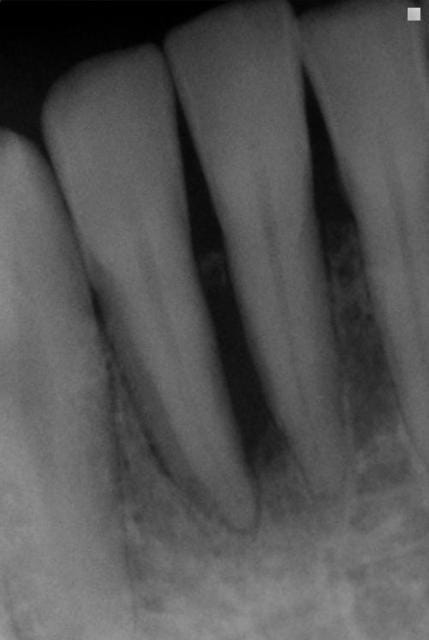

J'étais plus intervenu depuis longtemps parcequ'on m'avait dans les hautes sphères d'eugénol,demandé de me calmer,mais je peux pas laisser passer ça.On est dans un cas typique de guérison à la Sainte Carole, priez pour nous.La radio de départ elle est pourrie de chez pourrie.Comment on peut faire un diagnostic dans ces conditions?Comment on peut affirmer qu'il y a eu guérison, s'il n'y avait pas de lésion au départ.C'est absolument n'importe quoi.Il suffit de passer ces deux images à photoshop pour se rendre compte que les niveaux ne correspondent pas,et que sur la première image on est surexposé,ce qui brûle obligatoirement certaines zones de l'image,et que sur la deuxième on est sous exposé.Dans ces conditions,c'est ni six mois,ni trois,ni un jour,c'est en une seconde que je vous obtiens autant de guérisons miraculeuses que vous voulez.Y a vraiment personne qui réfléchit ici avec sa tête au lieu de s'extasier sur rien?pierres,va faire un stage de prise de radio avant de penser que tu es devenu un parodontiste émerite.

Meme si tu n y met pas les formes ta raison, sur la premiere radio on voit un defaut oseux evident masi on remarque aussi le sommet du septum interdentaire ... La preuve que la radio a été sur exposée

la différence d'exposition entre les deux clichés est évidente aussi, et c'est un défaut de la présentation.

Ceci dit , cela rend intéressant à postériori l'usage des réglages contrastes pour visualiser l'os à perdre ou à regagner. Le numérique nous le permet. La question étant y a t il encore une trame ou plus rien.

en fait sur ce cas, ce qui m'a inquiété c'est ce que je ne voyais plus sur la radio

alors que ce qui aurait dû me rassurer c'est ce qu'on y voyait encore